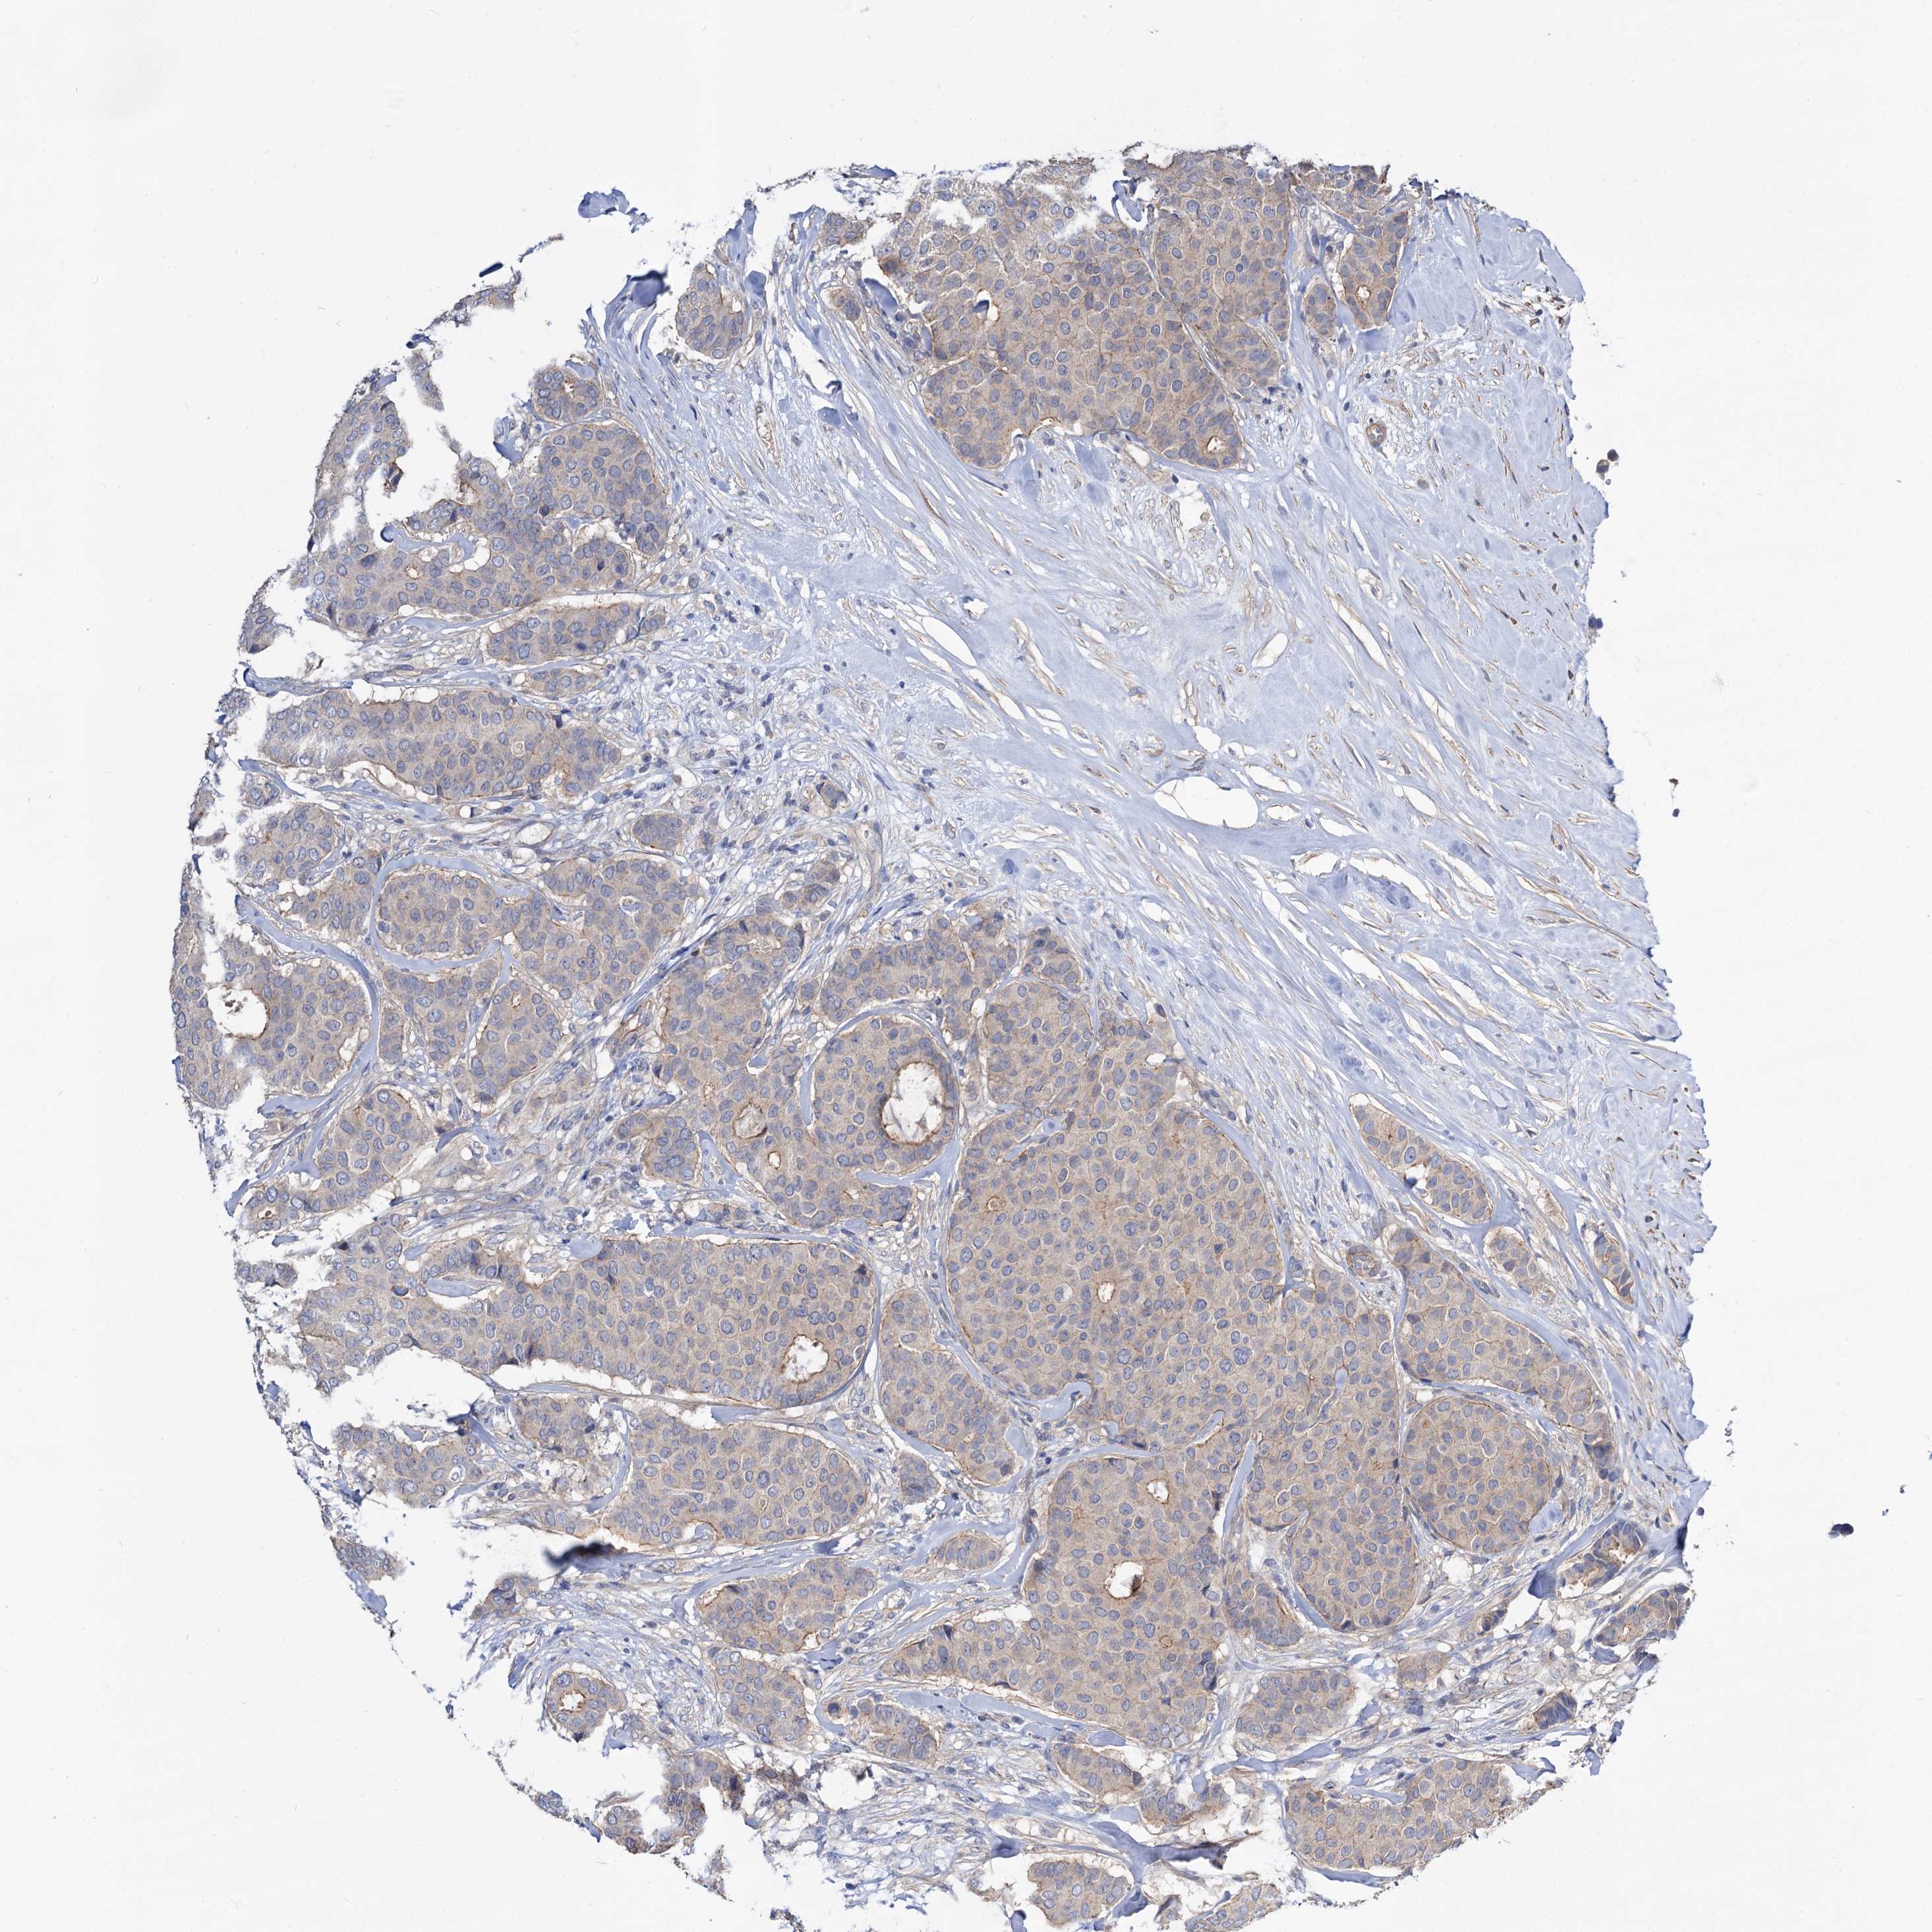

CANCER BREAST CANCER Show tissue menu

BRCA TCGA BRCA VALIDATION PROTEIN EXPRESSION